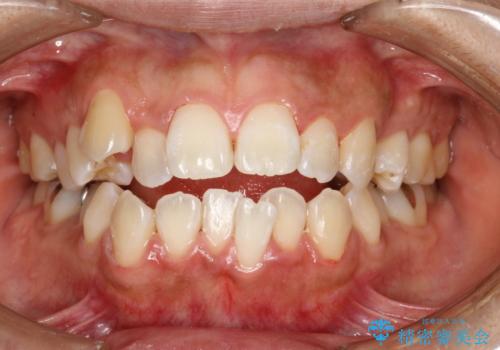

歯科矯正前のPMTC

治療症例の内容

- 20代女性

- 1日

- 1回

- 矯正前にしっかりとクリーニングを行いたいとのことで来院されました。PMTC30分コースを行いました。

- 5千円+tax費用は治療当時の料金となります

プラーク(細菌の塊)や歯石がたまると歯の表面はザラつきいてきます。そのザラつきは歯周病や虫歯菌の棲家となります。そのまま放置すると、歯肉が腫れてきたり、歯肉から出血したり、口臭が強くでたりします。とくに歯肉の境目は、歯磨きで汚れを除去することが難しく、プラーク(細菌の塊)や歯石が溜まりやすい場所です。

歯並が、がたついている場合はなおさら汚れが溜まりやすいです。矯正治療前や定期的にPMTCをすることで、矯正治療中の歯肉トラブルを防ぐことにつながります。